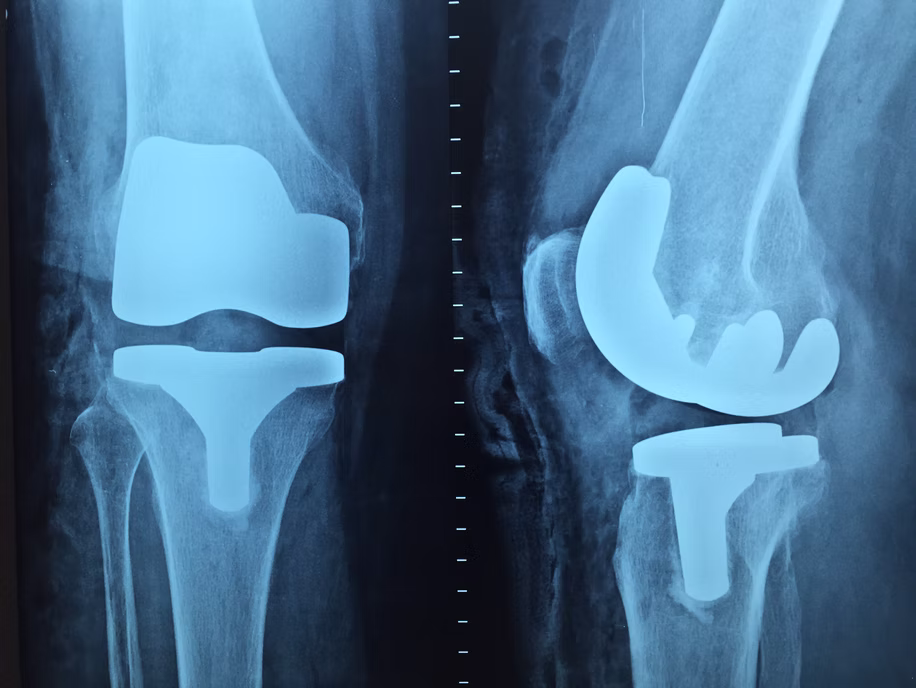

CHIRURGIE DE REMPLACEMENT DU GENOU

Aussi appelée arthroplastie du genou ou remplacement total du genou, cette intervention chirurgicale vise à soulager la douleur et à restaurer la mobilité de l’articulation. Elle est recommandée aux patients souffrant d’arthrose, de lésion du ménisque, de détérioration du cartilage, ou de maladie dégénérative des articulations.